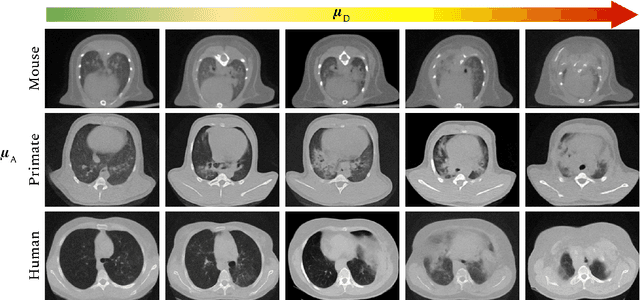

Abstract:The development of new treatments often requires clinical trials with translational animal models using (pre)-clinical imaging to characterize inter-species pathological processes. Deep Learning (DL) models are commonly used to automate retrieving relevant information from the images. Nevertheless, they typically suffer from low generability and explainability as a product of their entangled design, resulting in a specific DL model per animal model. Consequently, it is not possible to take advantage of the high capacity of DL to discover statistical relationships from inter-species images. To alleviate this problem, in this work, we present a model capable of extracting disentangled information from images of different animal models and the mechanisms that generate the images. Our method is located at the intersection between deep generative models, disentanglement and causal representation learning. It is optimized from images of pathological lung infected by Tuberculosis and is able: a) from an input slice, infer its position in a volume, the animal model to which it belongs, the damage present and even more, generate a mask covering the whole lung (similar overlap measures to the nnU-Net), b) generate realistic lung images by setting the above variables and c) generate counterfactual images, namely, healthy versions of a damaged input slice.